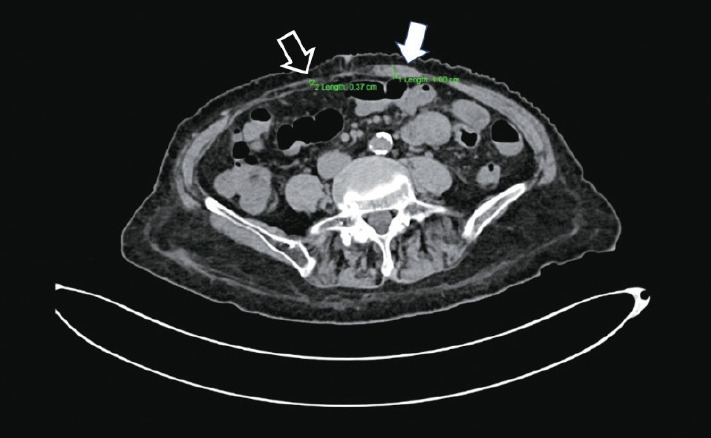

Muscle Dystonia Manifesting as Unilateral Rectus Abdominis Hypertrophy and Abdominal Pain in Parkinson's Disease: A Case Report.

帕金森病患者单侧腹直肌肥大和腹痛表现为肌张力障碍1例报告。